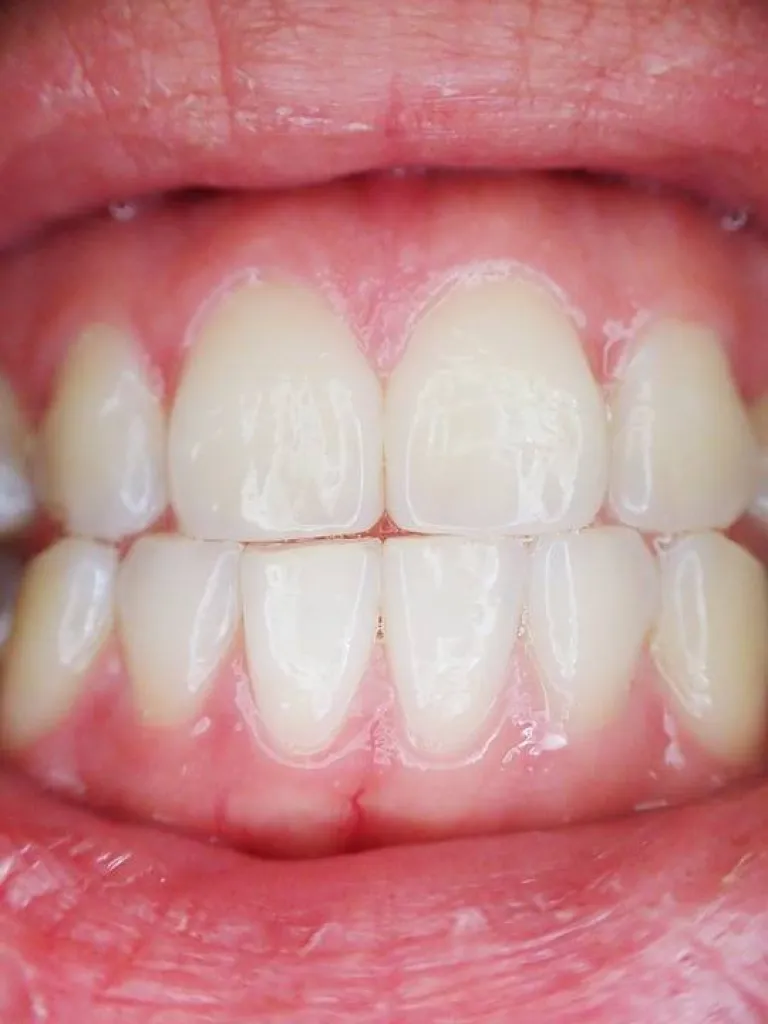

Praticien Invisalign® Marseille.Dr TOURROLIER Didier.

Plus de 4 millions de patients traités par la technique Invisalign® dans le monde .Découvrez cette nouvelle conception de l'orthodontie esthétique.

Le cabinet pratique l'orthodontie par gouttières transparentes pour l'adulte sur Marseille 13008 et ses alentours (Aubagne, Aix-en-Provence, Arles...), contactez-nous.